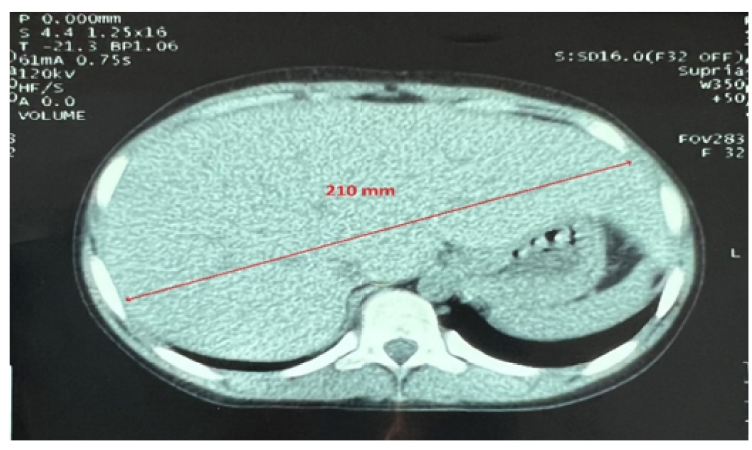

Isolated Hepatomegaly Revealing a Mauriac Syndrome (Case Report)

F Haddad, K Belhaj, FZ El Rhaoussi, M Tahiri Joutei Hassani, W Hliwa, A Bellabah, W Badre, M Azim, M Regragui and M Karkouri. 10(3): 08-11.